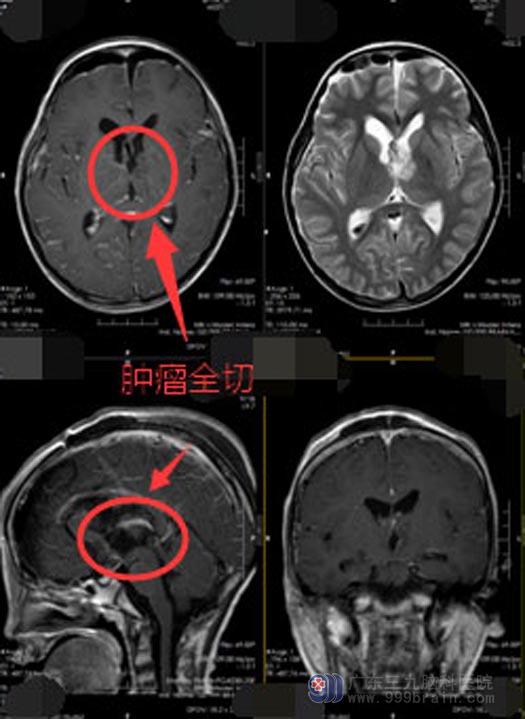

详尽的术前讨论并制定缜密的手术计划后,医院副院长、神经外五科主任鲁明带领手术团队为小星实施“三脑室-松果体区肿瘤病变切除术”,肿瘤在三脑室及松果体区,位于颅脑深部,肿瘤周围布满重要的颅神经及脑血管,风险非常高;如果在切除过程中损伤了正常脑神经或血管将会造成很严重的后果。所幸手术进行得非常顺利,完整地切除了肿瘤并很好的保护了正常的脑组织。

术后,小星很快就麻醉清醒,手脚活动没有丝毫影响,思维清晰。病理检查结果:儿童型弥漫性胶质瘤,WHOII级。目前已转入肿瘤科进一步放化疗。

▲手术后